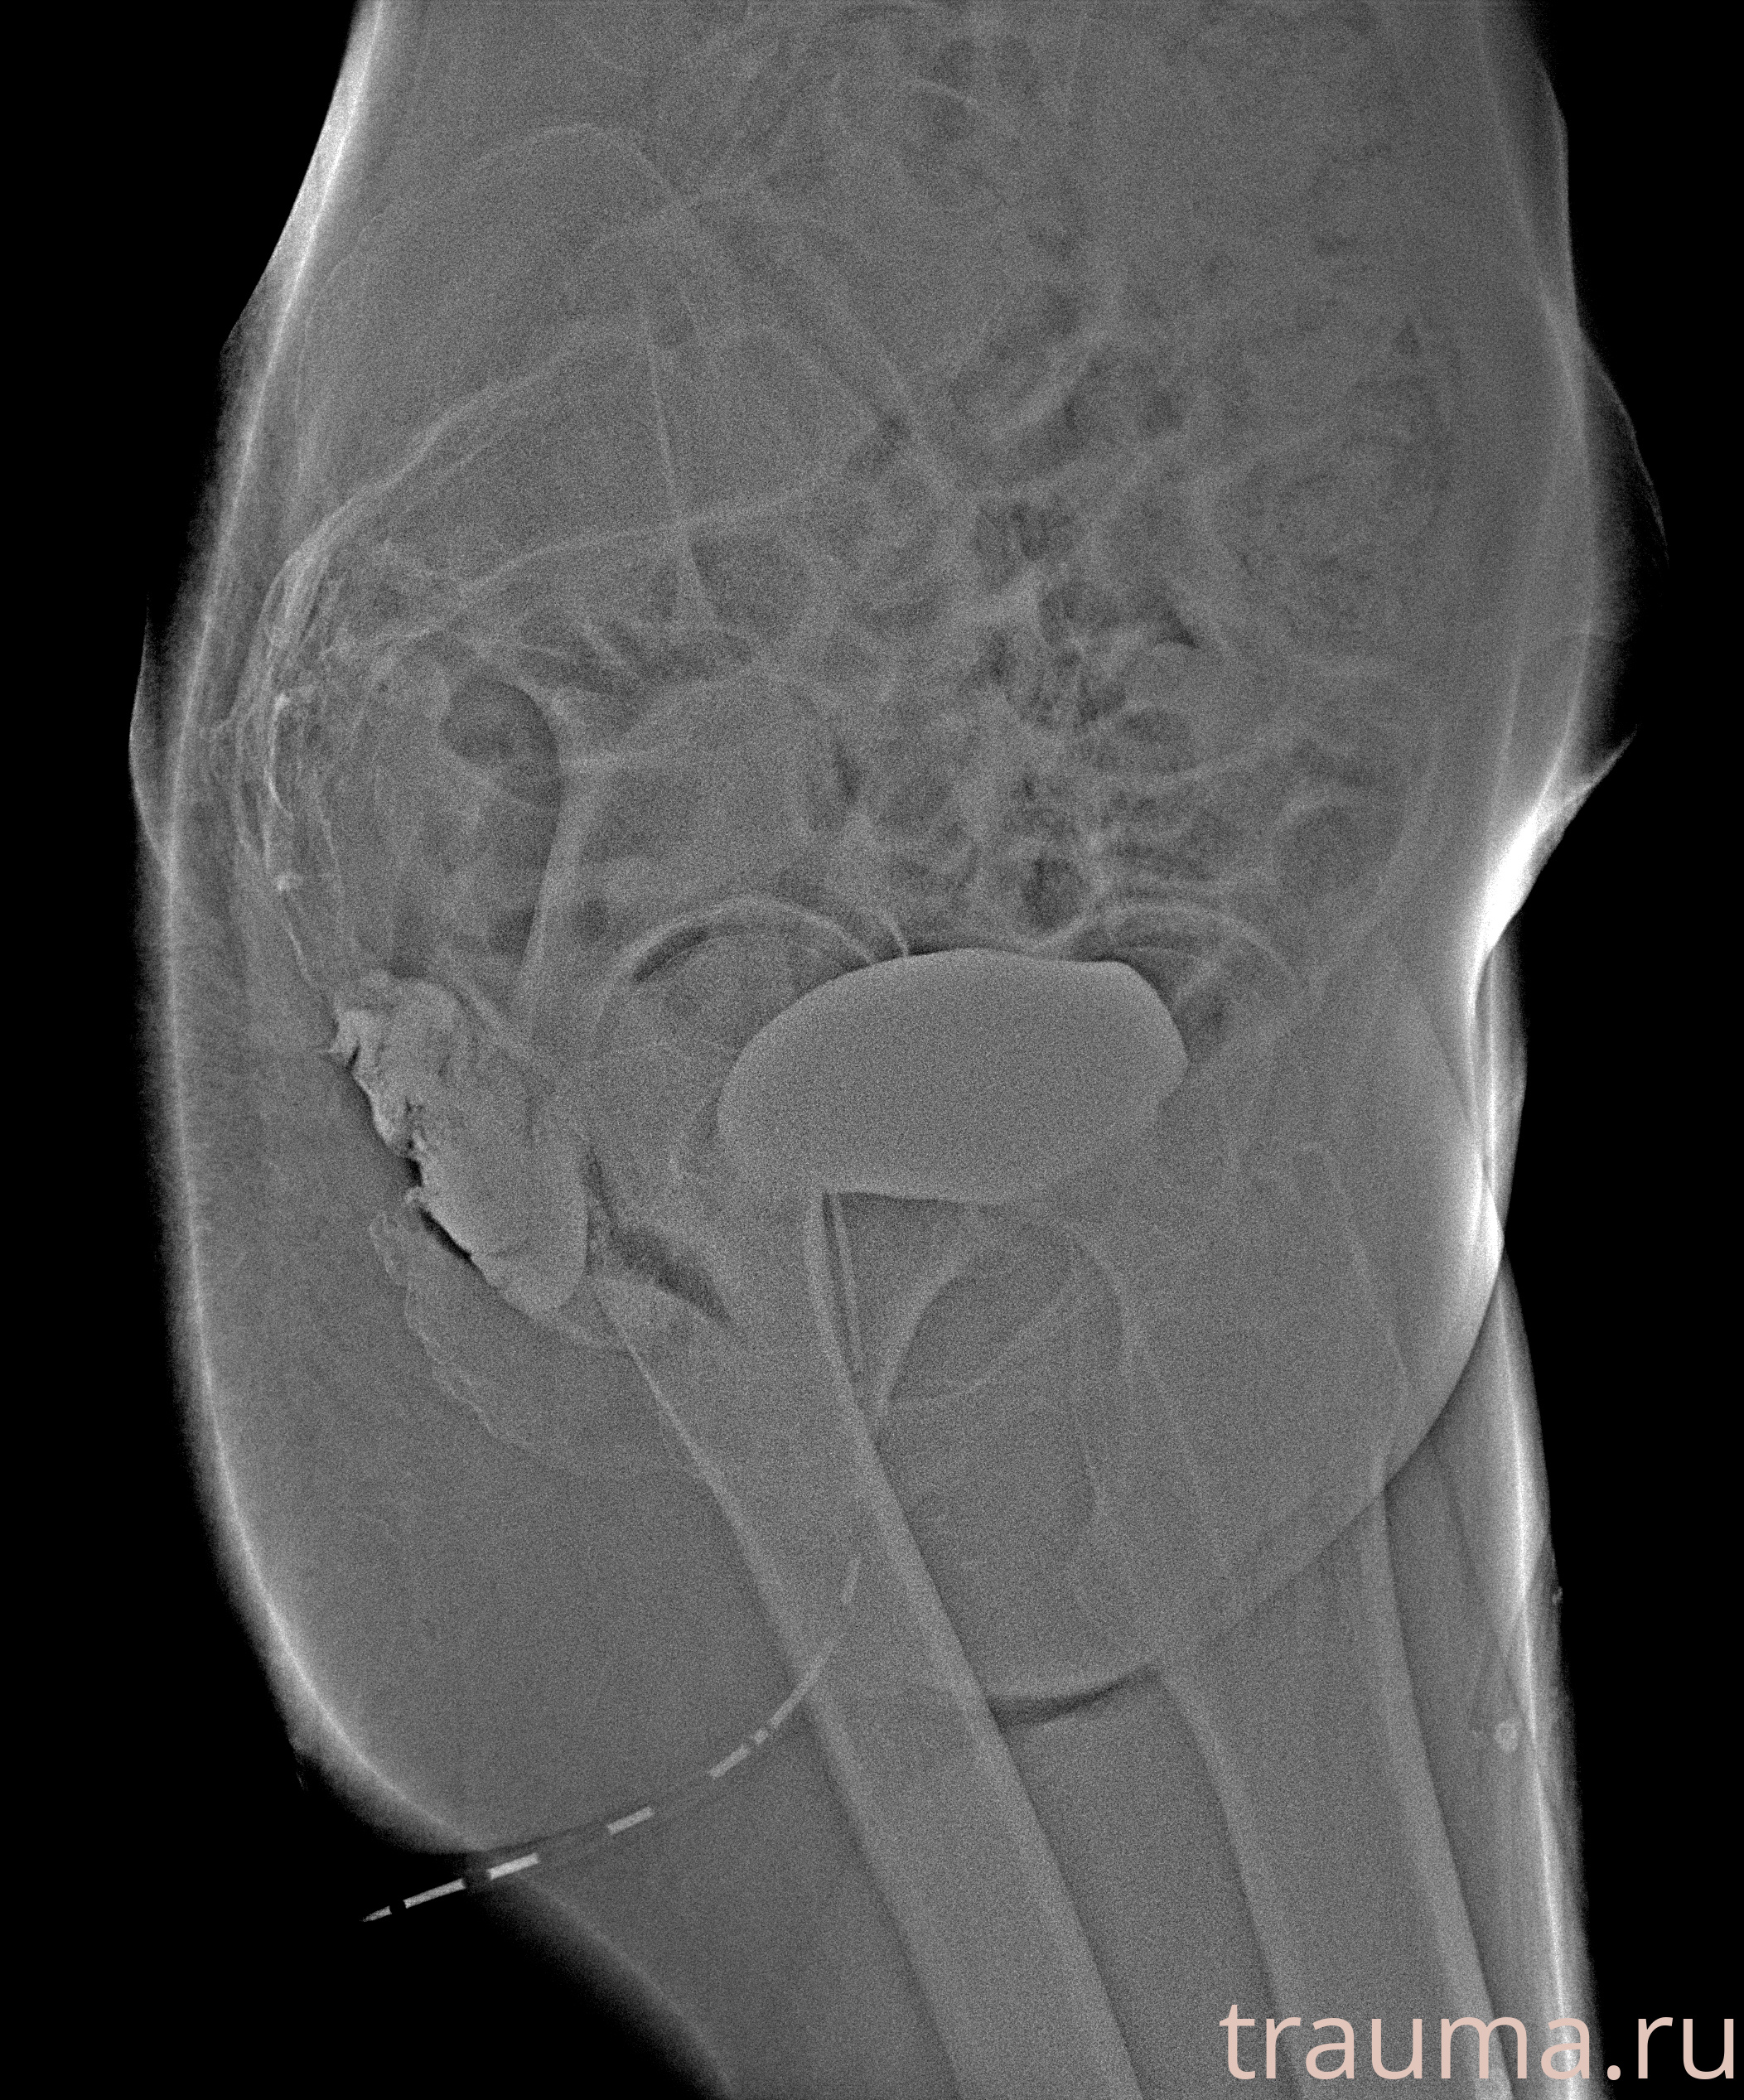

Рентгенограммы

Рентген на дому: по вашему адресу приезжает врач-рентгенолог, травматолог-ортопед с мобильным рентгеновским аппаратом, проводит диагностику травмы или заболевания, делает необходимые рентгенограммы, дает рекомендации по дальнейшему лечению. Получить качественные снимки в домашних условиях возможно благодаря уникальной методике, разработанной МосРентген Центром для института  Склифосовского